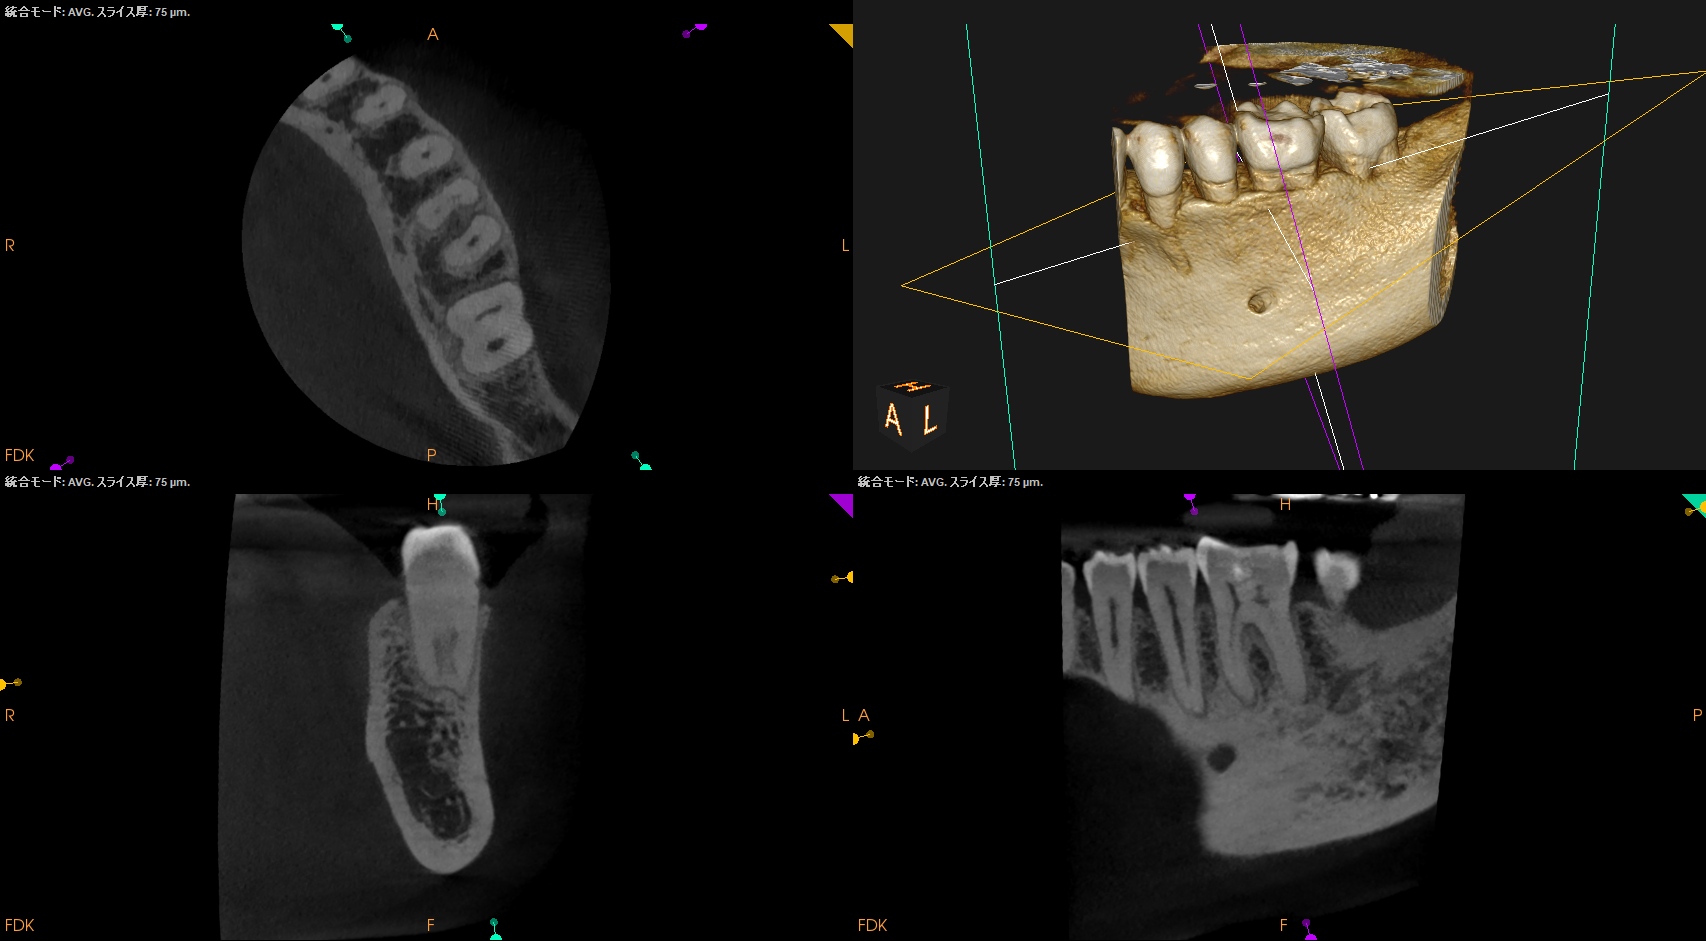

チャンバーオープンした。

やはり血まみれだ。

以下のように根管形成した。